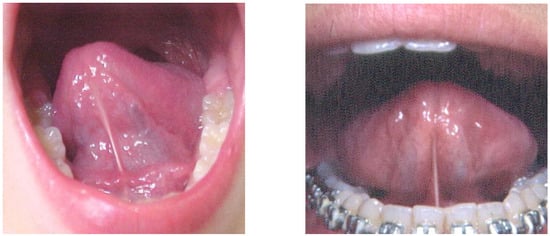

- did not allow adequate movement of the tongue;

- had an insertion in the inferior alveolar ridge or beneath;

- did not allow tongue suction on the palate even if there was an insertion in the midline under the tongue;

- when the tongue was raised the shape of the tip was more square;

- when the tip of the tongue was raised toward the palate only the edges can raise;

- for the tongue to reach the palate the patient needed to almost close the mouth;

- when the tongue is sucked up on the palate the distance between the incisal edges was less than 13mm (Figure 2).